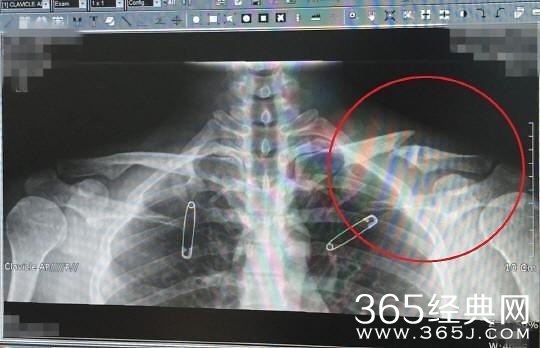

刘亚仁X光

刘亚仁之前曾两次受伤,2013年在拍摄电影《强哲》时右肩肌肉撕裂,2014年拍摄电影《老手》时病情恶化,2015年被诊断为患上骨癌。去年,刘亚仁的左侧锁骨完全骨折导致肩部受伤,但是刘亚仁在打过止痛针后坚持参加活动。火影忍者剧情介绍